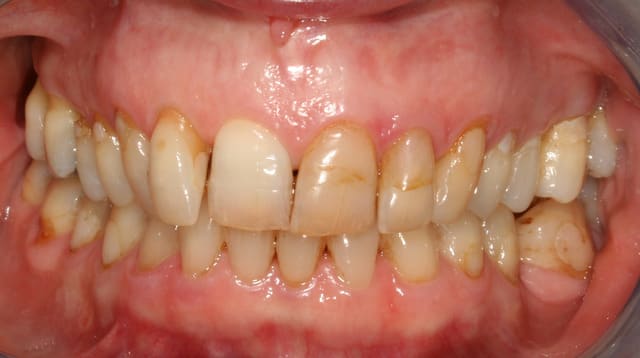

si je résume, on a

un sourire gingival

un parodonte fin

un épisode passé de perte d'attache

une usure de certaines dents

un axe lingualé des dents

une usure au collet

un édentement non compensé ancien

faut il mettre tout cela sur le compte de son occlusion, de sa classe II ?

et surtout tout cela est il pathologique ?

pour ma part, je ne voyais pas tout ça comme pathologique, mais a la vue des réponses concordantes ou tout le monde part sur de l'ortho a fond, je me dis que j'ai du manquer un truc

et du point de vue esthétique, le gummy smile est il une hérésie ?

peut on selon vous envisager un traitement esthétique qui ne cherche pas forcément à corriger ce critère ?